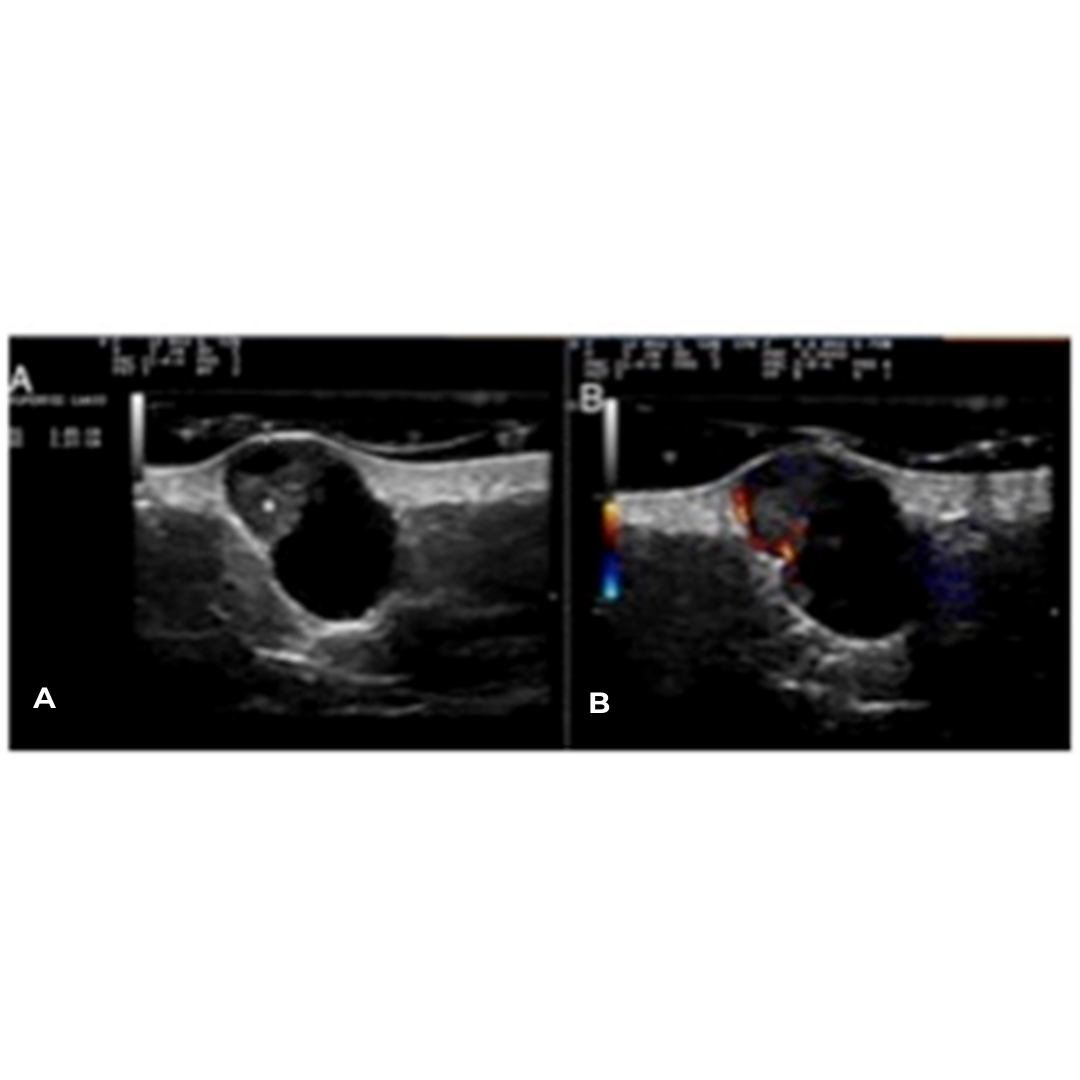

Ecográficamente se define como una lesión dermo-hipodérmica de naturaleza quística, ovalada, bien definida, presenta porción solida frecuentemente hiperecogénica con vascularización, pudiendo presentar calcificaciones (imagen 5).

Imagen 5: A) Lesión dermo-hipodérmica, ovalada, anecoica, con una zona hiperecogénica triangular que protruye desde su pared (asterisco). B) Aumento de flujo a nivel periférico y en la porción sólida triangular (modo Doppler).